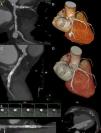

Case ReportA 66-year-old male ex-smoker with hypertension, type 2 diabetes mellitus and dyslipidaemia, without history of trauma, vasculitis or connective tissue disorders, was admitted due to a non-ST segment elevation myocardial infarction with mild troponin I elevation (Grace 2.0: 93; estimated 1-year mortality 3.1%; estimated 3-year mortality: 7.1%; Crusade: 27, 6.1% bleeding risk). The ECG showed sinus rhythm with lateral negative T waves, a transthoracic echocardiogram revealed normal left ventricular ejection fraction and the cardiac catheterisation depicted an extensive and calcified coronary disease, including a chronic total obstruction at the proximal segment of the right coronary artery together with a severe and diffuse disease with a giant aneurysm at the first obtuse marginal branch as the culprit lesion (Figure 1A), TIMI flow III. The left anterior descending artery revealed no significant stenosis. Since the patient remained stable on medical treatment, we decided further study was necessary and a coronary CT was ordered, confirming the previous findings (Figure 2A-B) and highlighting a giant saccular coronary aneurysm (17x14mm) with a wide neck at a big obtuse marginal level.

Then, intracoronary imaging (IVUS, Boston-Scientific, MA, USA; Figure 1C and OCT, St Jude, St. Paul, Minn., USA; Figure 1D), was performed, depicting a severely diseased and calcified vessel, with a tight calcified stenosis (ALM:1.78cm2), previous to the neck of the aneurysm. A first attempt to cross the graft directly failed, probably because of marked tortuosity. The whole vessel was consecutively predilated with a 2.5x12mm balloon. A mother-and-child system was then advanced (6F-Guideliner, Vascular Solutions Inc., Minn., USA), allowing to cross the lesion with the stent-graft (3.5x20mm) and its proper positioning (14atm). Later, two DES were consecutively implanted, covering all the LCx stenosis, including the stent graft, with a good angiographic outcome and complete aneurysm obliteration, Figure 1B. In addition, implanting a DES inside the stent-graft could hopefully potentially diminish the proliferative/thrombotic trend described for these covered scaffolds.

The result was optimised with several high pressure 3.5x15mm noncompliant balloon inflations, with a good angiographic outcome. This was double-checked with intracoronary imaging (IVUS; Figure 1E and IVUS; Figure 1F).